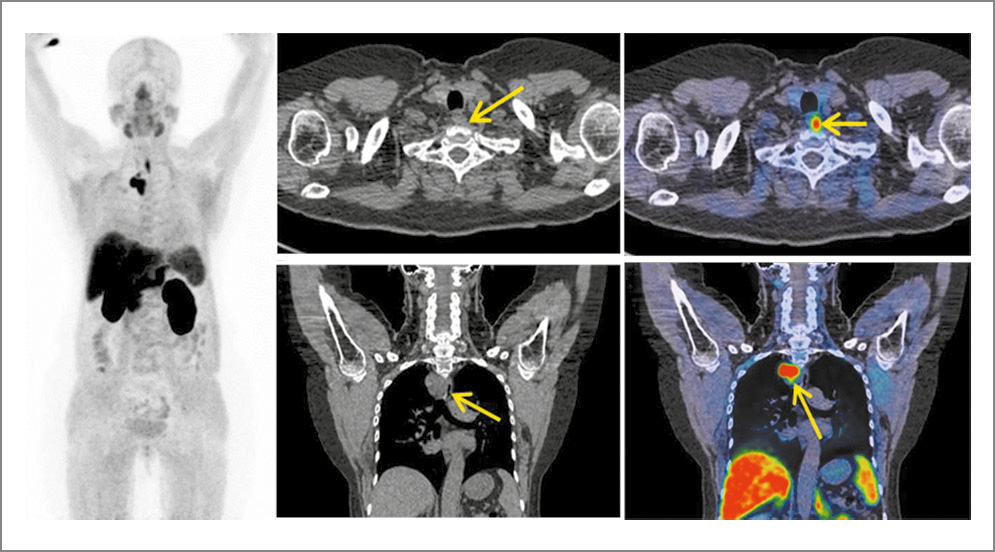

Радионуклидные методы исследования, равно как и другие, используются в основном для топической диагностики аденом околощитовидных желез. Среди них гибридное исследование ОФЭКТ/КТ является высокоинформативным методом топической диагностики и оценки метаболической активности аденом околощитовидных желез. Оно выполнено всем больным (рис. 1).

Рис. 1. Пациент П., 58 лет. а – планарная сцинтиграфия шеи и средостения, b, с – гибридное исследование ОФЭКТ/КТ, совмещенное изображение, аксиальные и корональные срезы. На представленных изображениях очагу гиперфиксации соответствует неоднородное мягкотканное образование в верхнем средостении размерами 27,7×26,0×33,0 мм, расположенное паратрахеально справа, с достаточно четким контуром. Заключение: сцинтиграфические признаки эктопированной в центральное средостение гиперфункционирующей аденомы паращитовидной железы.